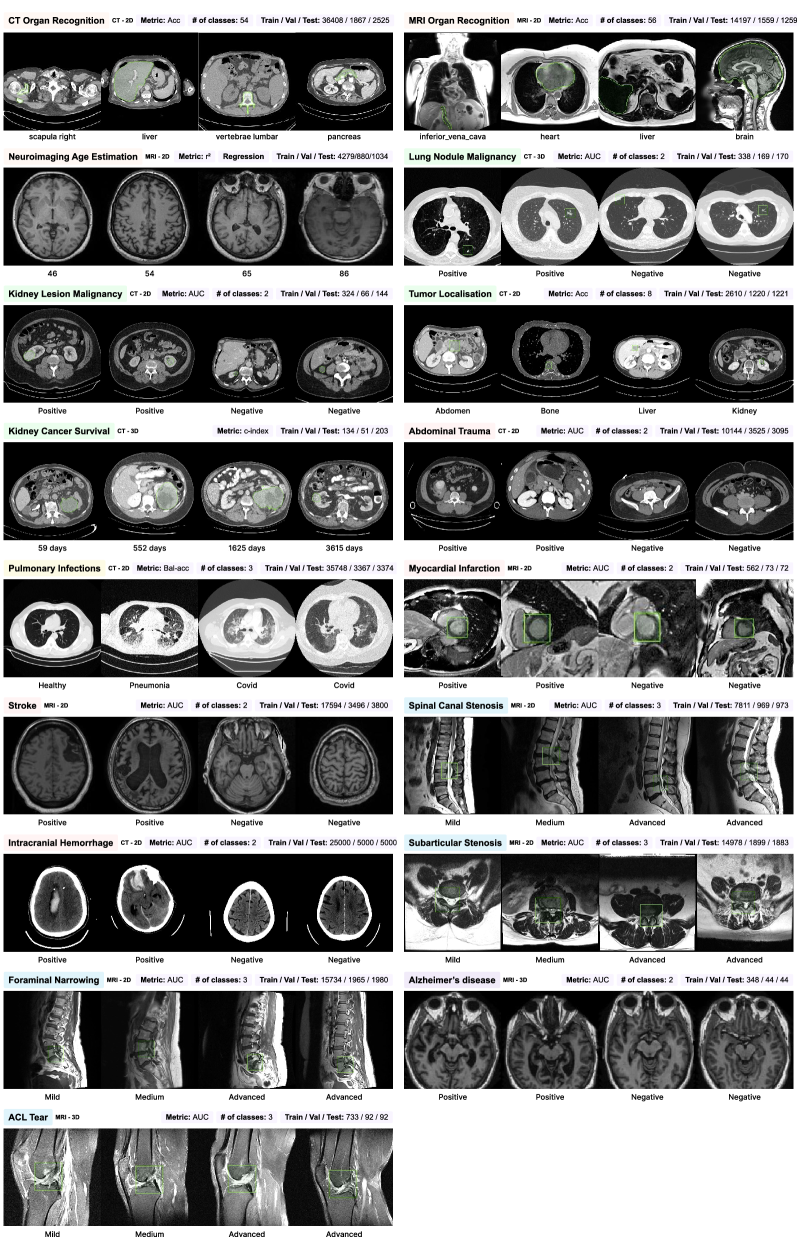

Refer to caption

Figure 2: List of downstream tasks considered in the CuriaBench benchmark. For each task, we report the modality (CT/MRI), the type (2D/3D), the metric (Accuracy, AUC, Balanced Accuracy, r2r^{2}), the number of classes for classification tasks, and the sizes of the training, validation, and test sets. The registration task and the prompted segmentation task are showcased in Fig. 3.

This section describes CuriaBench, a benchmark consisting in 19 downstream tasks we used to evaluate Curia and other FMs. Fig. 2 presents example images for each task, detailing their modality, the number of images in the training, validation, and test sets, and the performance metric used in the benchmark.